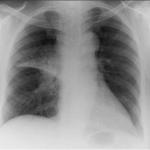

U Nemačkoj su započeta testiranja na ljudima prve nove vakcine protiv tuberkuloze u više od 80 godina, dok u svetu strahuju da ta bolest postaje sve otpornija na postojeće terapije.

Novi lek nazvan "VMP1002" temelji se na "bsž" vakcini, koja se još od 1921. godine koristi za imunizaciju ljudi obolelih od tuberkuloze.